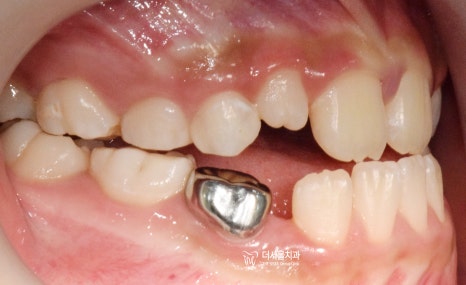

『구강 내 사진』

성장교정 이 필요한 이유는,

구강 내 사진에서도 뚜렷히 찾아볼 수 있습니다.

유치가 빠지면서 영구치아가 올라오고 있는

혼합치열기에서, 영구치가 올라올 수 있는

충분한 공간을 확보하면서

턱의 위치를 바로 잡는것이 핵심포인트입니다.

우선 여기서 봐야 될 큰 문제는

1) 절단교합(Edge to edge bite) 입니다.

윗니가 아랫니를 물고 있어야 되는데,

서로 절단연끼리 맞닿고 있죠.

측정치는 왜소치의 형태를 가지고 있었기에,

크라운을 만들어서 수복해서 심미성을

부여해드렸습니다. (표기 : 1, 2번)